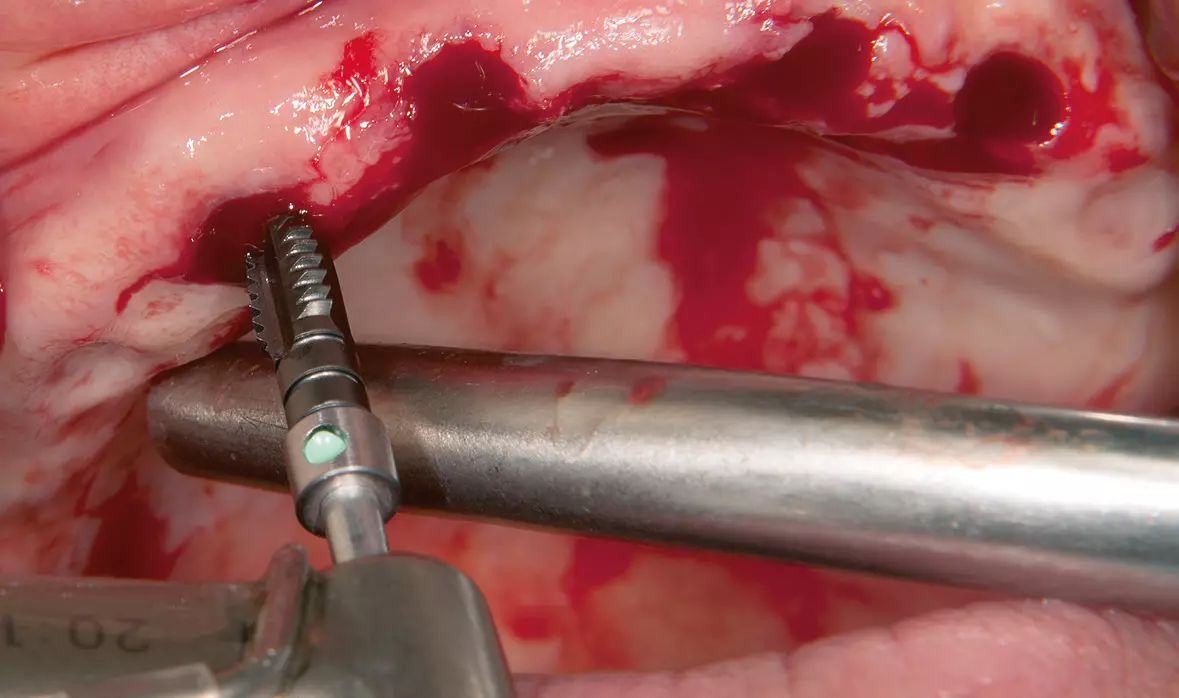

Abb. 14: Vorschneiden des Gewindes mit einem Gewindeschneider (50 N/cm Drehmoment). Dr. Michael Leistner

Abb. 14: Vorschneiden des Gewindes mit einem Gewindeschneider (50 N/cm Drehmoment).